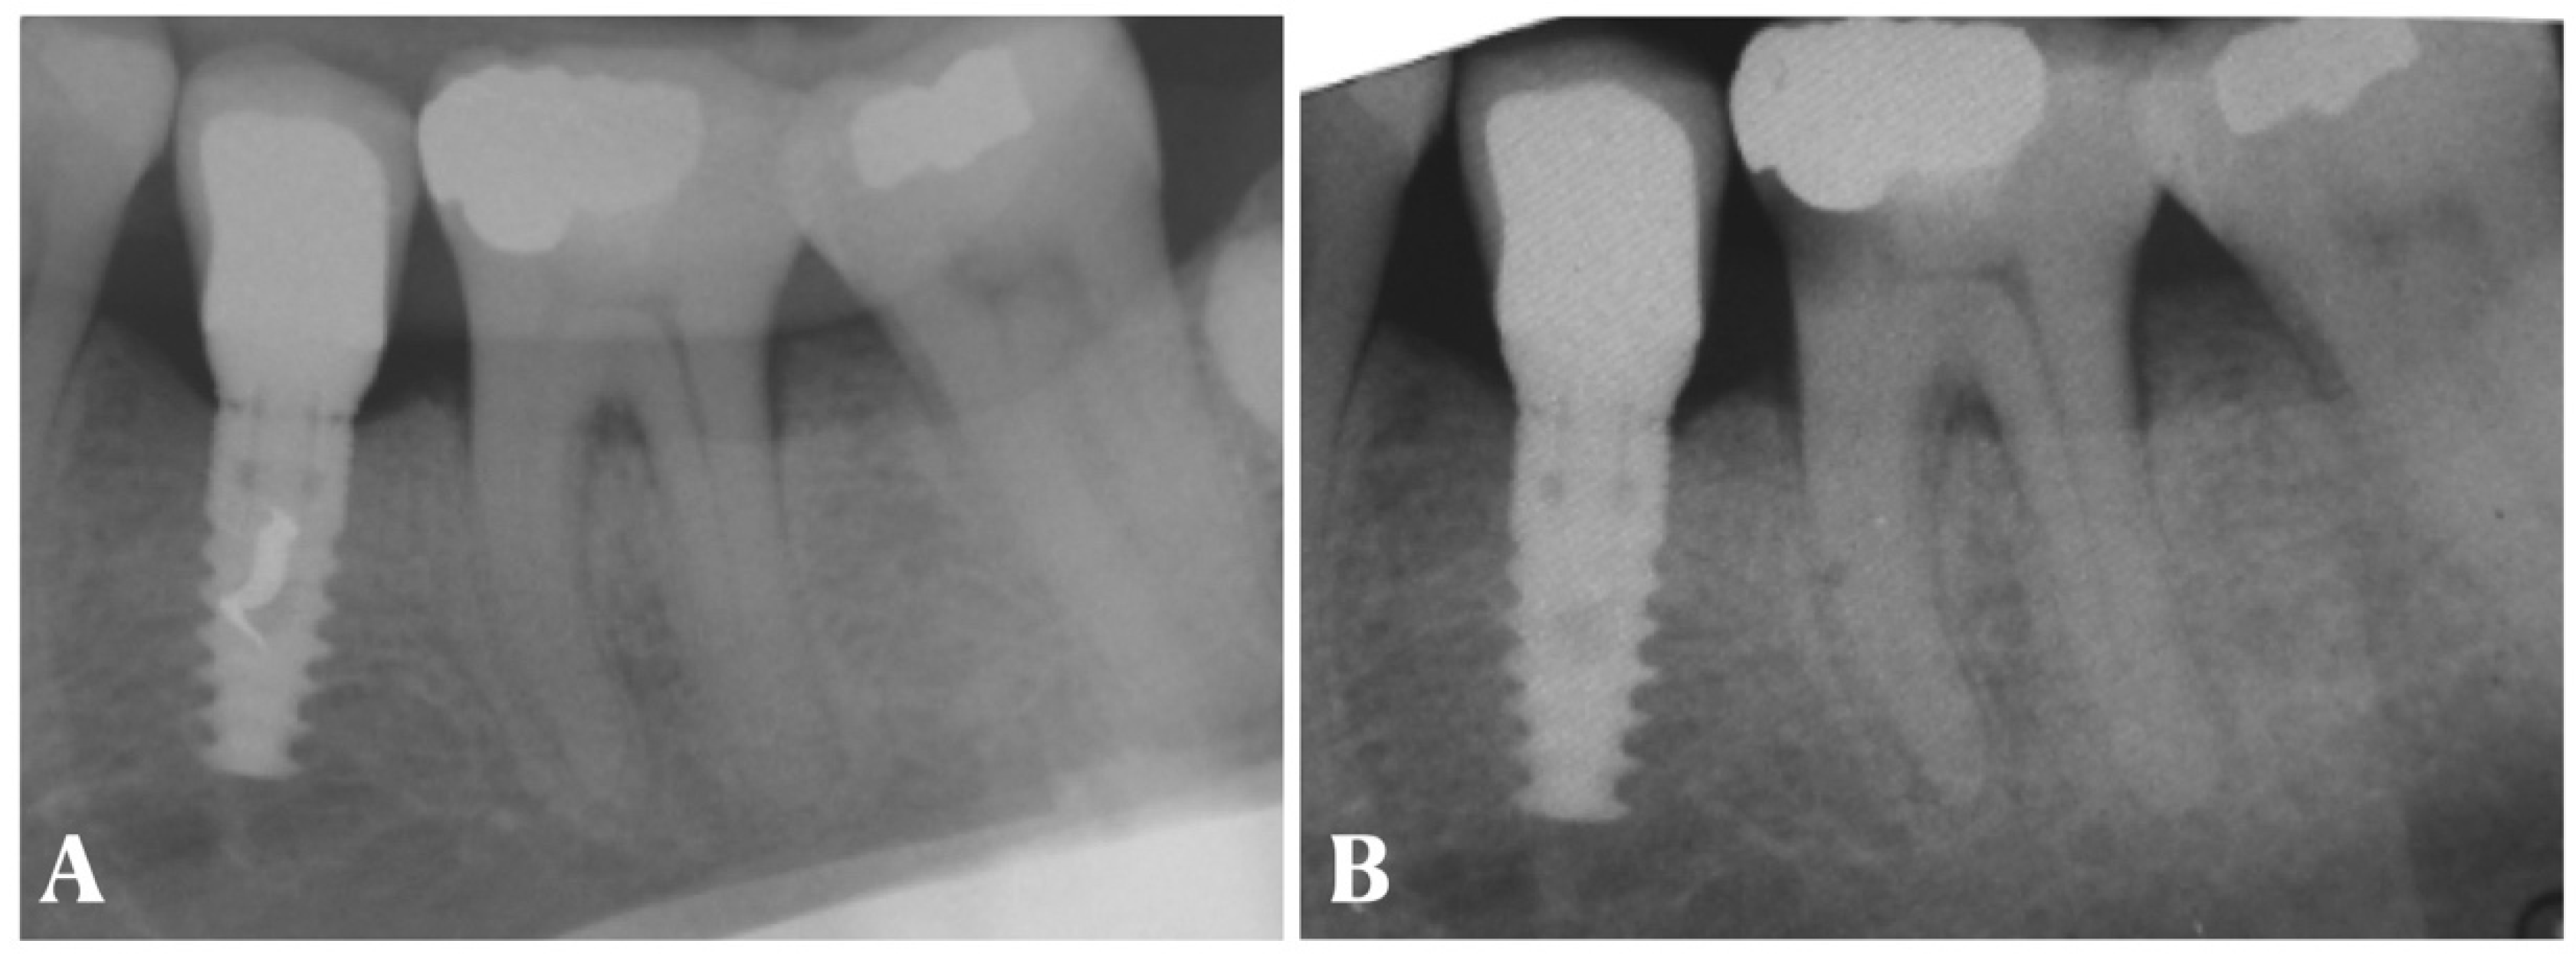

- Periapical X-ray;